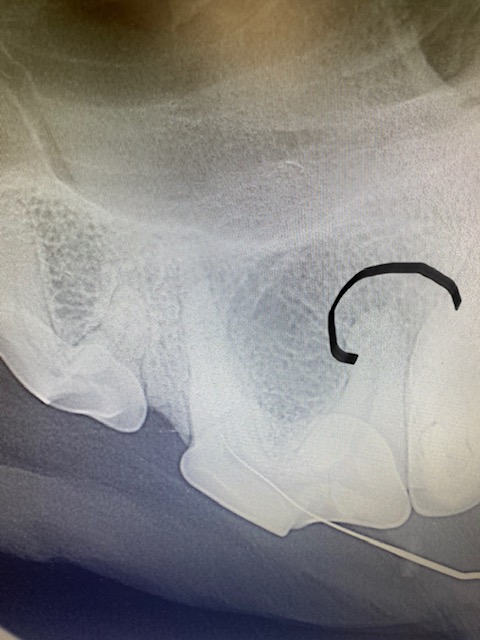

Tooth 208 (upper left premolar) had a complicated crown fracture. When under anesthetic a small pathfinder file was inserted into the pulp. A pre op X-ray showed a slightly lytic circular region around the distal root (black line outlies this). This tooth could have had a root canal operation performed if the owner had wanted to save the tooth, however in this instance an extraction procedure was elected. A maxillary nerve block using bupivicaine was performed, then the tooth was sectioned into 3 and each root removed separately. On the distal root a granuloma can be seen around the apex (this is what was visible on the X-ray). After extraction an X-ray was taken to confirm no root remnants remained and the alveolar bone was smoothed with an oval diamond head bur. The gingival flap sutured closed with simple interrupted 4/0 absorbable suture material with no tension. NSAID pain relief was given post. Antibiotics were not dispensed.